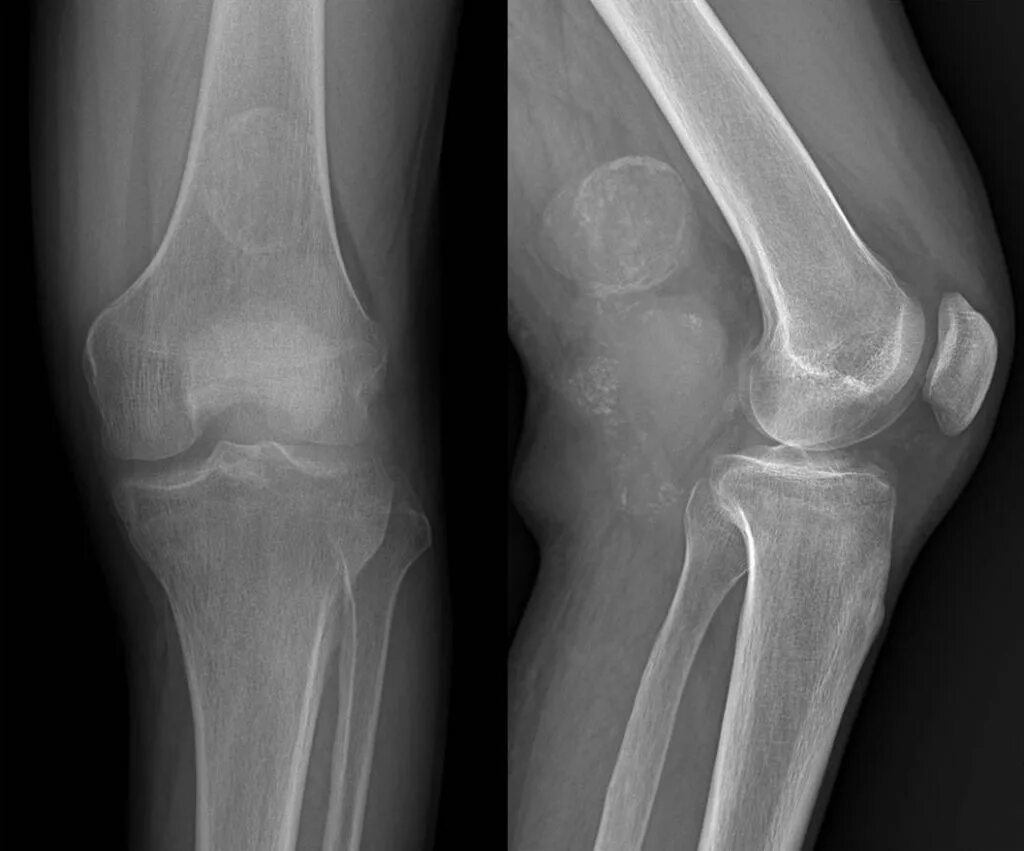

Синовиомы